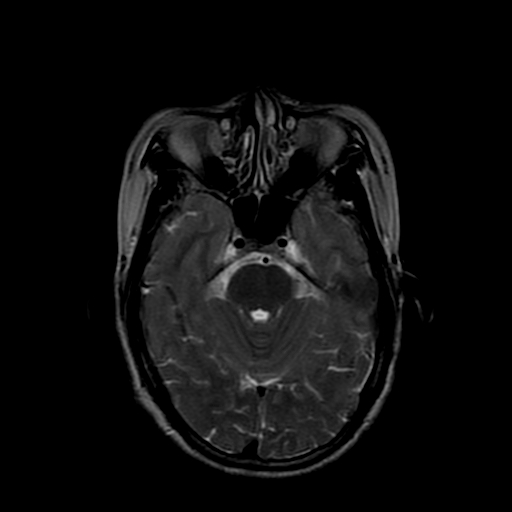

女性,47岁。mri号03027,外伤致头痛9天,抽搐一天,原无类似病史。

双侧海马的信号都有异常。

双侧海马硬化!

颞叶前部萎缩,海马萎缩,t2wi海马高信号,支持海马硬化。

双侧海马硬化.

双侧海马区t1低,t2高信号。为什么都考虑硬化?发病原因?鉴别诊断:炎症,梗塞等能一下子除外吗?